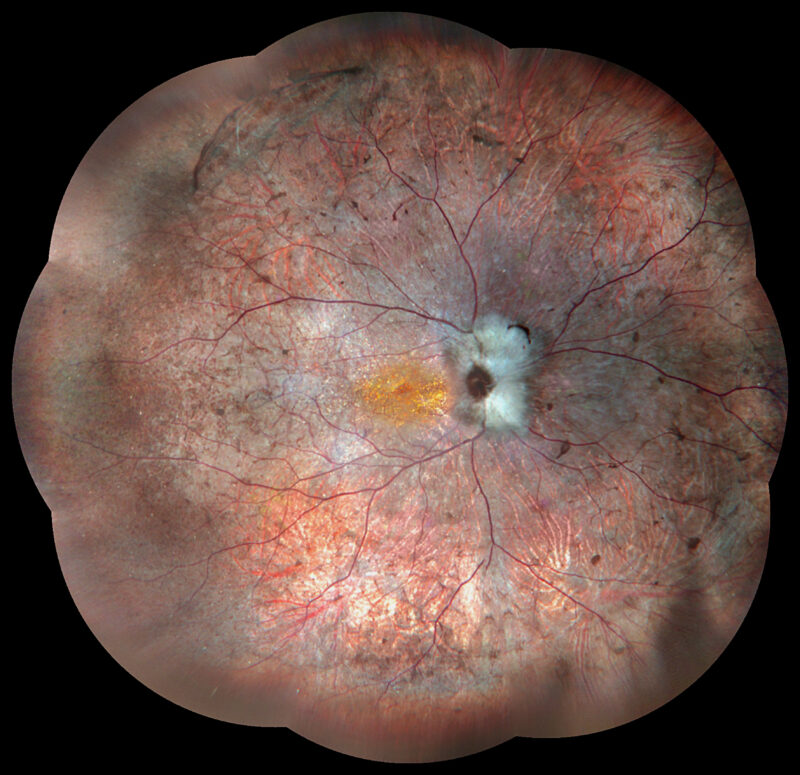

Ultra-groothoek en multimodale fundusangiografie gebaseerd op confocale scanning laser oftalmoscopie (CSLO).

Ultragroothoek

- 45° UHD (Ultra High Definition)

- 90° HD (High Definition)

- 135° WA (Groothoekangiografie) – in één opname

- Panoramisch beeld tot 240° – via mozaïekstitching